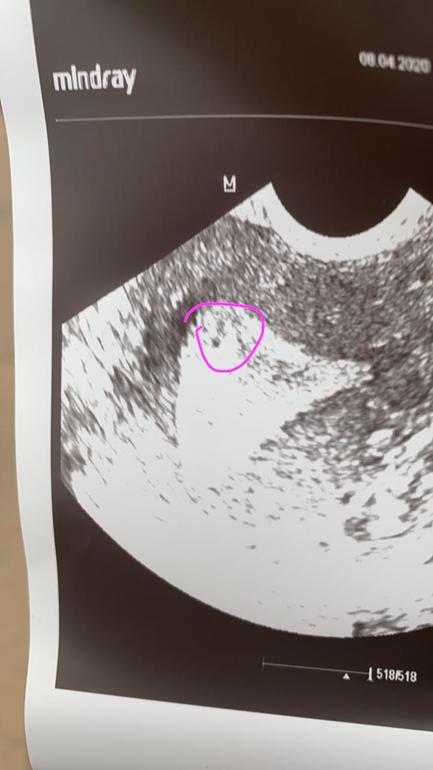

Такое было в 4-5 недель, при размере 1,8мм.

Снимок засвечен. Лучше описание УЗИ приложите